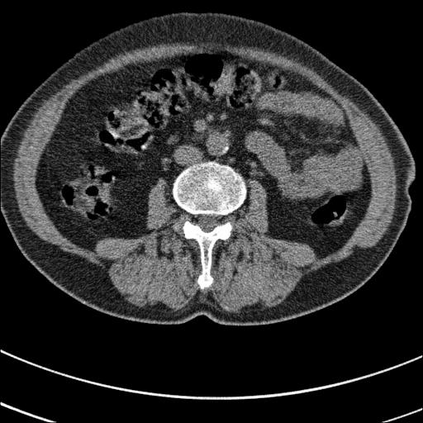

Low-Dose Computed Tomography (LDCT) technique, which reduces the radiation harm to human bodies, is now attracting increasing interest in the medical imaging field. As the image quality is degraded by low dose radiation, LDCT exams require specialized reconstruction methods or denoising algorithms. However, most of the recent effective methods overlook the inner-structure of the original projection data (sinogram) which limits their denoising ability. The inner-structure of the sinogram represents special characteristics of the data in the sinogram domain. By maintaining this structure while denoising, the noise can be obviously restrained. Therefore, we propose an LDCT denoising network namely Sinogram Inner-Structure Transformer (SIST) to reduce the noise by utilizing the inner-structure in the sinogram domain. Specifically, we study the CT imaging mechanism and statistical characteristics of sinogram to design the sinogram inner-structure loss including the global and local inner-structure for restoring high-quality CT images. Besides, we propose a sinogram transformer module to better extract sinogram features. The transformer architecture using a self-attention mechanism can exploit interrelations between projections of different view angles, which achieves an outstanding performance in sinogram denoising. Furthermore, in order to improve the performance in the image domain, we propose the image reconstruction module to complementarily denoise both in the sinogram and image domain.